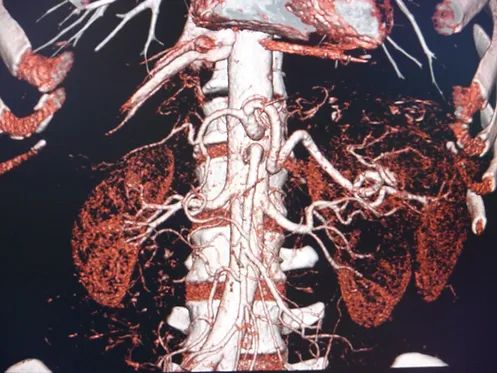

A hormone-secreting tumour that can occur in the adrenal glands. Phaeochromocytomas usually develop in the small glands on top of the kidneys (adrenal glands). They most commonly affect people between the ages of 20 and 50, but can occur at any age. Because of hormones secreted, symptoms include high blood pressure, sweating, rapid heartbeat and headache. Surgery to remove the tumour is usually required.